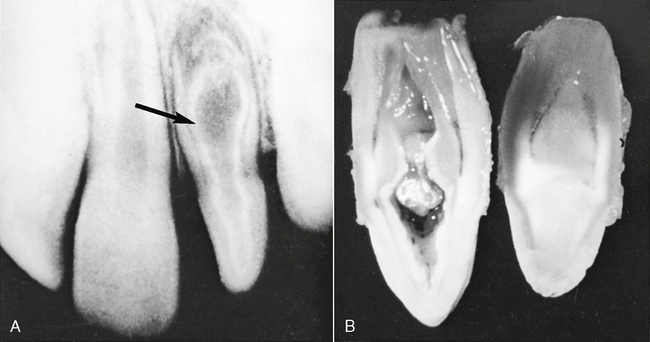

Dens in Dente

Dens in dente (Fig. 7-7) is a developmental variation thought to occur when the outer surface of the tooth crown invaginates or turns itself inward before mineralization. The term, dens in dente means tooth within a tooth. An x-ray image of a dens in dente shows what appears to be a tooth actually within a tooth (see Fig. 7-7, A). This invagination allows communication between the oral cavity and the inner enamel-lined cavity, which could be considered an extremely deep pit. Permanent maxillary lateral incisors are the teeth most often affected by dens in dente.